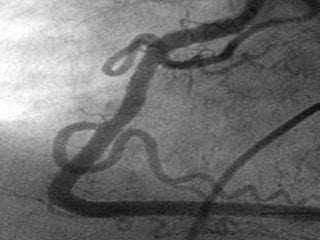

   Arteria coronaria

derecha

   lesión crítica en su

tercio medio con

imagen de trombo

en su interior

Arteria coronaria derecha  lesión crítica en su tercio medio con imagen de trombo en su interior